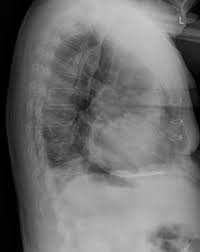

- 호흡 곤란: 심낭 주위의 염증으로 인해 심장의 움직임이 제한되거나 심낭액이 증가할 경우, 호흡이 어려울 수 있습니다. 특히 심낭액이 증가하면 폐의 움직임을 방해할 수 있습니다.

2. 심낭액 배출 시술

- 심낭액이 과도하게 증가하여 호흡이나 심장 기능에 영향을 미치는 경우, 심낭액을 배출하는 시술을 고려할 수 있습니다. 이는 심낭액의 압력을 줄여 호흡과 심장 기능을 개선하는데 도움을 줄 수 있습니다.